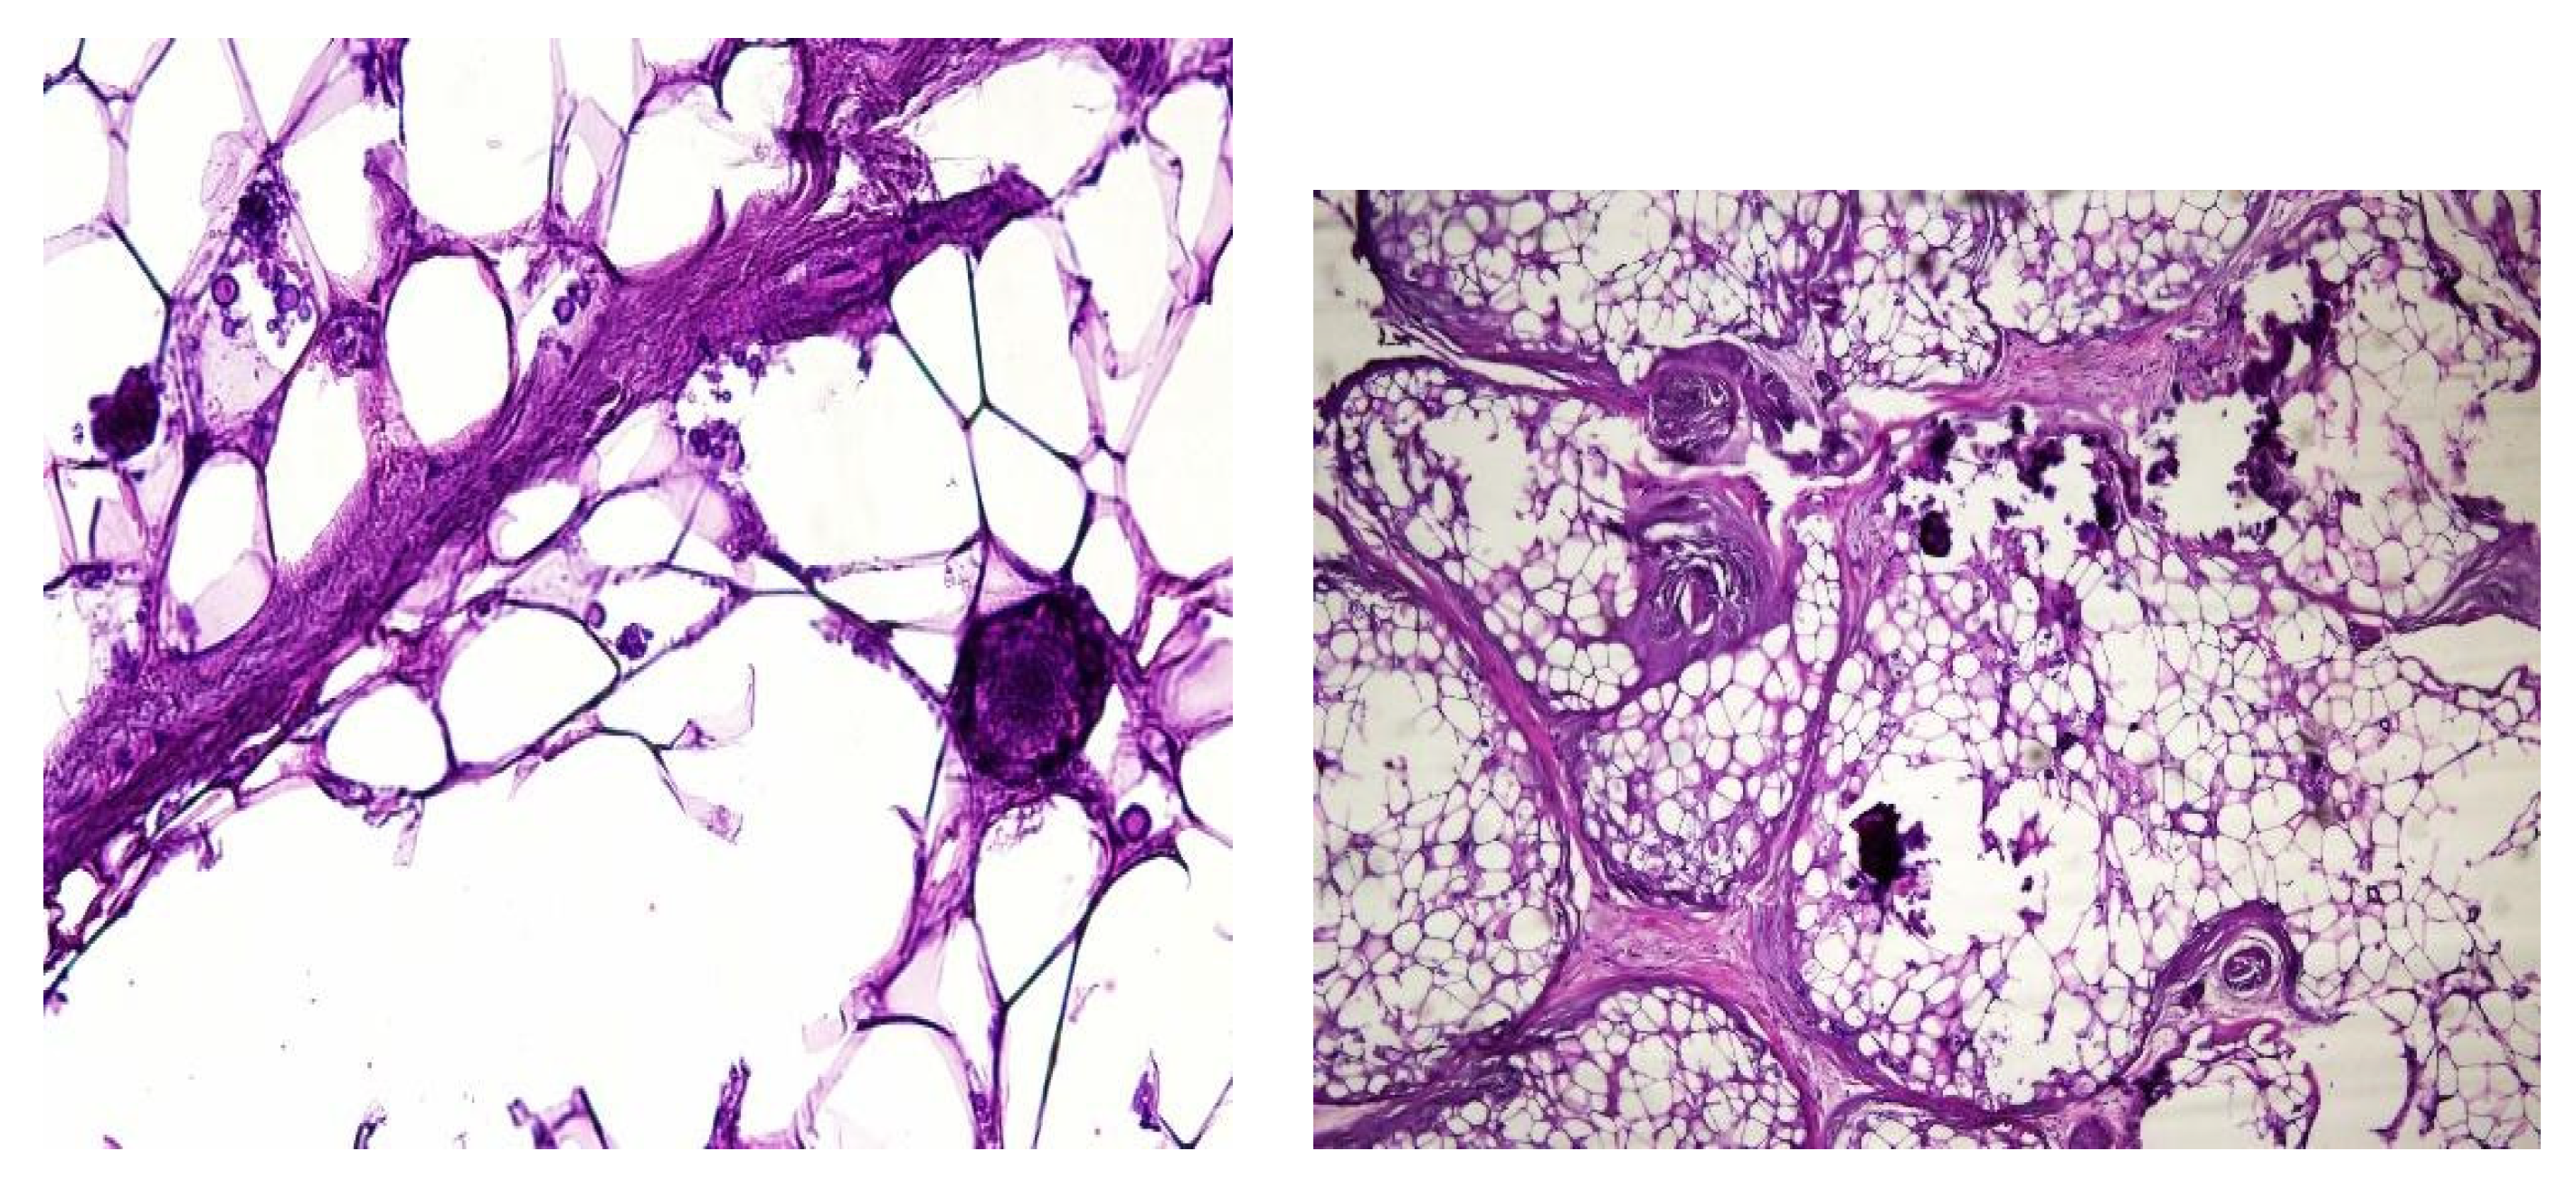

In both of the described cases, optical microscopy revealed lamellar fibrosis, deposits of fibrin on the surface of the peritoneum (Images 3 and 4) and dystrophic calcifications in the peritoneum (Images 5 and 6).

Images 5 and 6. dystrophic calcifications in the peritoneum (haematoxylin and eosin staining, original magnification x100).